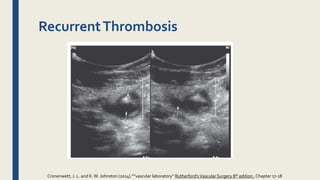

RecurrentThrombosis

■ Recurrent thrombosis is defined as a repeated thrombotic

event. It may occur in the contralateral or ipsilateral limb

■ Three DUS criteria can be used to diagnose recurrent DVT:

■ extension of the thrombus more than 9 cm,

■ noncompressibility of a vein segment that had previously been

compressible or had previously recanalized,

■ increase in thrombus thickness by 4 mm.

• #27 Recurrent thrombosis in the common femoral vein in a patient with limb swelling and chest pain. The patient previously had a femoropopliteal thrombosis documented in our hospital. The vein contains both echogenic (downward arrow) and echolucent (upward arrow) material (left panel). It is dilated (significantly larger than the common femoral artery, arrow, right panel) and noncompressible.